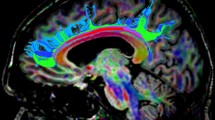

The corticospinal tract (CST), arcuate fasciculus (AF) and its long segment (AFl) were reconstructed in 17 healthy subjects imaged twice using a deterministic approach. Coefficients of variation (CVs) of diffusion-derived tract values were used to assess the microstructural reproducibility. Spatial correlation and fibre overlap were used to assess the architectural reproducibility.

Next, the CST, the AF and AFl were extracted for each individual from regions of interest (ROIs) according to a priori information of tract location [50, 51]. The tracts of interest were only delineated in the left hemisphere considering the left hemisphere lateralisation of these tracts when subjects are strongly right-handed [52, 53]. The ROI sets of all tracts of interest were manually placed only by the first author (G.K.) as a previous study reported a high interobserver reliability in tract-specific analysis [54]. This was done following the guidelines and protocols described in previous studies, where figures showing the ROI placement are also present [9, 32, 33, 51]. The CST was extracted by placing two ROIs on axial slices. The first ROI included the cerebral peduncle at the level of the decussation of the superior cerebellar peduncle. The second ROI was drawn right after the bifurcation to the motor and sensory cortex to include only primary motor cortex, and not sensory tracts [51]. The AF was extracted by placing two ROIs on coronal slices. The first ROI was selected where the AF, appearing as a green triangular shape on coronal images (indicating anterior/posterior orientation), was seen to be largest. The second ROI was selected at the level of the splenium of the corpus callosum, where the AF makes a sharp turn towards the temporal lobe [9, 32]. The AFl was defined by using the first ROI used for the delineation of the AF, and by placing a second ROI on an axial slice through which the AF passes in the superior/inferior direction [33].